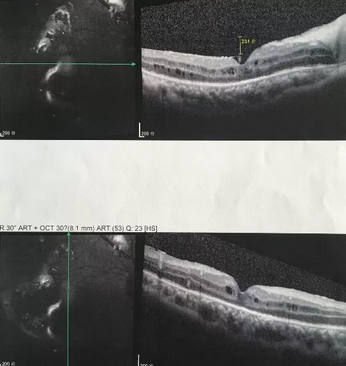

独眼,视网膜全脱离已成窄漏斗状、陈旧性葡萄膜炎、瞳孔后黏连无法散大,且并发白内障使得视网膜周边部细节情况无法看清,左眼已无光感,角膜白斑,瞳孔闭锁,还填充着硅油。右眼既往葡萄膜炎病因不清,一年中发病3、4 次都是用激素医治。左眼多年前是“天那水”溅入后又发生玻璃体出血手术后……令人担心的是这次我们克服重重困难救治全部脱离的视网膜 后,可能会面对长期慢性葡萄膜炎、长期药物医治的继发性高眼压,以及葡萄膜炎的再次复发等,稍有不慎就是不逆性致盲了。

手术室外,是家属们焦灼的等待。手术室内,是赵院长肩负重任带领大家紧张抢救。这是一场与时间赛跑、与病情赛跑,从黑暗到光明的抢救医治。赵铁英院长全神贯注、时而需要屏住呼吸如履薄冰般地操作、目不转睛同时双脚控制显微镜和机器参数,双手紧密配合,在如同混浊的海底世界的眼球腔内修复重建……

后,终于新旧病变处理完毕,展平复位了即将全部粘连在一起的视网膜,手术获得了 !没有下夜班仍继续在医院组织会诊参加手术的助手龙飘飘医生也长舒了一口气说:挽救了一个眼,挽救了一个人,挽救了一个家庭!